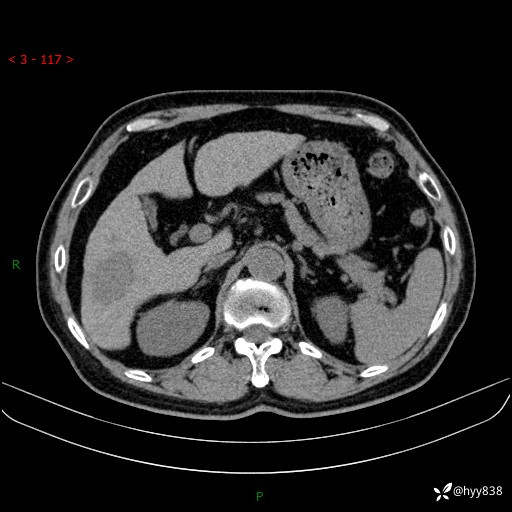

静脉期